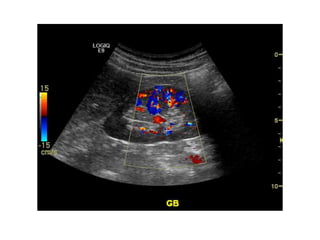

Doppler modes

Color Flow (CF)

A Primer ofDiagnostic Ultrasonic Imaging Modalities Doppler modes: Color Flow (CF) Spectral Doppler

A Primer ofDiagnostic Ultrasonic Imaging Modalities Doppler modes Color Flow (CF)